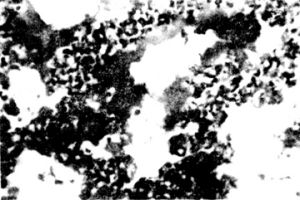

新生兒肺透明膜病鏡檢:肺小動脈收縮,毛細血管及小靜脈瘀血,絕大多數肺泡萎縮,有廣泛的再吸收性肺不張。典型病變為未萎陷及部分擴張的肺泡、肺泡管壁及終末毛細支氣管壁上有一層透明的均勻無結構或顆粒狀嗜伊紅膜樣物附著,它由損壞脫落的肺泡上皮細胞、纖維素和含蛋白質的基質組成。死胎中從未見過透明膜。死於生後8小時以內者,透明膜形成不全,多數還斷續游離於泡腔。肺泡間隔血管瘀血。